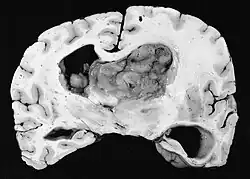

Subependymale Riesenzellastrozytome treten insbesondere bei Kindern und jungen Erwachsenen auf. Da der Tumor bevorzugt in der Wand des Ventrikelsystems in der Nachbarschaft der Foramina Monroi entsteht, ist mit zunehmendem Wachstum häufig der Liquorabfluss gestört. Der Tumor wächst in der Regel sehr langsam und zeigt sich in der Bildgebung als umschriebene Raumforderung mit Verkalkungen und Zeichen älterer Blutung. In manchen Fällen ist das SEGA die Erstmanifestation einer tuberösen Sklerose (TSC) und zählt daher zu einem diagnostischen Hauptkriterium. Allerdings entwickeln nur 6–16 % aller TSC-Patienten ein SEGA.